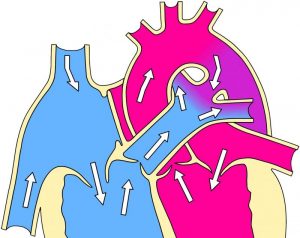

La trompa de Eustaquio es un canal pequeño que se encarga de conectar el oído medio con la parte trasera de la nariz y que se encuentra ubicada en la parte superior de la garganta o nasofaringe.

La mayoría de las veces, la trompa de Eustaquio se encuentra cerrada, y se abre solo durante actividades tales como bostezar, tragar y masticar, para permitir que el aire entre por el pasaje que existe entre el oído medio y la nasofaringe. Cuando la presión atmosférica cambia de forma veloz, causando una sensación repentina de bloqueo en el oído, estas actividades se pueden hacer a propósito para abrir el tubo e igualar la presión que existe dentro del oído medio.

Su función principal es la de establecer una adecuada comunicación entre la parte anterior y superior de la caja timpánica con la parte superior de la faringe para poder regular las presiones que se dan dentro del oído medio, y de esta manera cuidar las estructuras ante cambios bruscos equilibrando las presiones a ambos lados del tímpano.